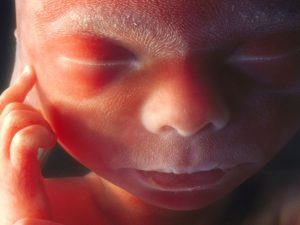

Малыш выглядит на фото как крошечный человек. Врач применяет строгое научное слово «плод», но многие будущие матери уже не могут так называть своего кроху. Для них в 19-20 недель беременности — это уже ребенок, потому что они чувствуют своего наследника буквально – на физиологическом уровне.

Плод на 19 неделе уже имеет полностью сформированный скелет. Хрящи укрепляются, конечности становятся более пропорциональными. Кожа еще тонкая и красная, вся в морщинках, но совсем скоро под ней начнет скапливаться слой подкожного жира, что приведет к разглаживанию складок.

В организме малыша активно собирается жирок. Кожа уже не такая прозрачная, теперь она красного цвета и имеет складки. Сверху кожа продолжает покрываться защитной смазкой, которая скапливается подмышками, шеей и под коленками. Она помогает малышу, защищает от бактерий окружающих его.В это время скелет продолжает костенеть, многие хрящики уже стали костями.

Также продолжает покрываться пушком лануго кожа маленького. Эти волосики видны даже на лице ребеночка, что иногда сохраняется аж до самих родов. Не переживайте, они потом исчезнут, так что младенец не будет все время мохнатеньким.

Ребенок на 19 неделе уже приобретает пропорциональное телосложение – его ручки и ножки имеют такие же пропорции, как при рождении. Постепенно накапливается жировая ткань, сейчас в основном в области внутренних органов. Подкожная клетчатка пока недостаточно развита, и малыш выглядит очень худеньким.

Постепенно начинается накопление подкожной клетчатки, и теперь кожа малыша немного светлее, чем ранее, хотя по-прежнему морщинистая.